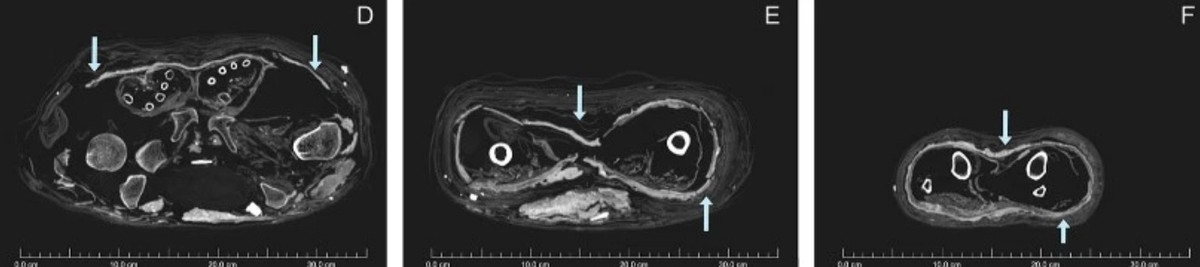

Các nhà khoa học Australia mới tiến hành chụp CT và xác định niên đại bằng phương pháp carbon phóng xạ cho một xác ướp Ai Cập và cỗ quan tài. Hiện chúng được lưu giữ và bảo quản tại Đại học Sydney.

Kết quả kiểm tra cho thấy xác ướp người phụ nữ có niên đại vào khoảng năm 1200 trước Công nguyên.

Trong khi đó, chiếc quan tài chứa xác ướp có niên đại vào khoảng năm 1000 trước Công nguyên.

Điều này đồng nghĩa với việc chiếc quan tài và xác ướp có niên đại không trùng khớp. Thi hài người phụ nữ có niên đại lớn hơn cỗ quan tài khoảng 200 năm.

Từ đây, các chuyên gia suy đoán có thể một tay lái buôn đã đặt xác ướp người phụ nữ vào quan tài có niên đại thấp hơn để bán được với giá cao.

Do đó, quan tài có khắc tên một người phụ nữ là Meruah không phải là danh tính thực sự của xác ướp đặt bên trong.

Dù các chuyên gia chưa tìm ra danh tính thực sự của người phụ nữ này nhưng các chuyên gia biết được rằng, người này qua đời khi khoảng 26 - 35 tuổi.

Xác ướp người phụ nữ này được bọc trong một lớp bùn. Kỹ thuật này được cho là bắt chước theo phong tục mai táng của hoàng gia Ai Cập thời cổ đại.